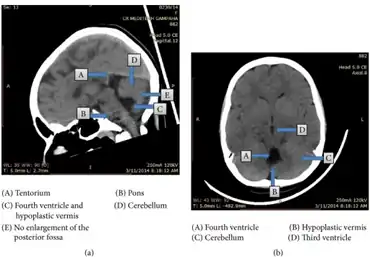

![]() | |

| T2-weighted sagittal MRI of Dandy–Walker variant (DWV) with dysplasia of the pons and cerebellar vermis in an 8-year old | |